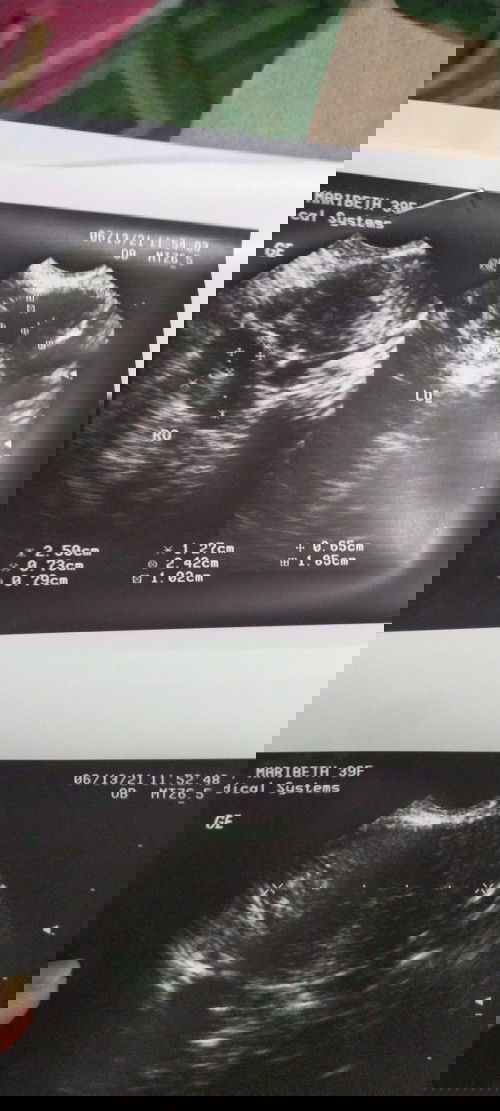

Hi mamshie much better kung ung pinaka utz status mo po ung nakapost para may mabasa kami kahit papano mahirap po kasi mag interpret lalo na pag film lang even mga OB ang unang ni check ung impression or ung pinaka result ng utz ksi dun talaga mag base un result🙂

Early pregnancy pa po. Parang bahay bata palang po nakita sayo if di ako nagkakamli 😊